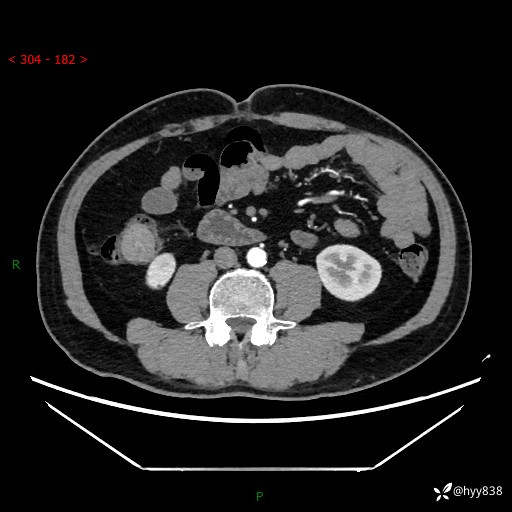

腹部CT增强扫描(外院CT平扫)

两期CT值:75hu 82hu